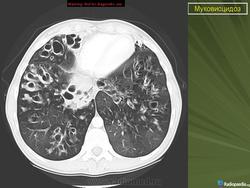

При тщательном обследовании обнаруживается учащенное дыхание, увеличение переднезаднего размера грудной клетки и слабо выраженное, но стойкое втяжение нижних межреберных мышц. Аускультативные патологические признаки могут вообще не выявляться или присутствовать в виде сухих и влажных мелко- и крупнопузырчатых хрипов. На рентгенограмме органов грудной полости выявляют уплотнение стенок бронхов, а также различной степени уплотнение или повышенную воздушность легочной ткани. Могут развиваться ателектазы в сегментах и долях легких, причем поражение правой верхней доли относится к диагностически значимым признакам муковисцидоза.

• ухудшение физикальной и рентгенологической картины в легких;

- Рентгенография органов грудной клетки в прямой и правой боковой проекциях.

• новые рентгенологические изменения в легких (инфильтраты, ателектазы, сливающиеся, гомогенные затемнения или параллельные линейные тени);